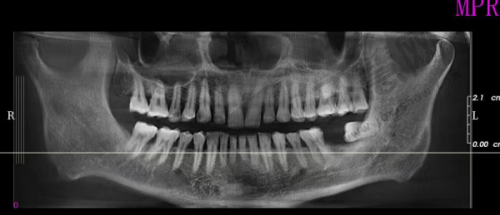

支付宝生活号:在支付宝搜“维尔口腔”,选择“沈阳分院”,直接拍“1元预约体验券”,到院可免费做口腔检查(含全景片拍摄),适合想先“考察”再决定的姐妹~

不管是种植牙、矫正还是补牙,医生都会先拍CT做详细检查,再出方案,拒绝“一刀切”,这点比有些医院“上来就推荐贵的项目”靠谱多了~